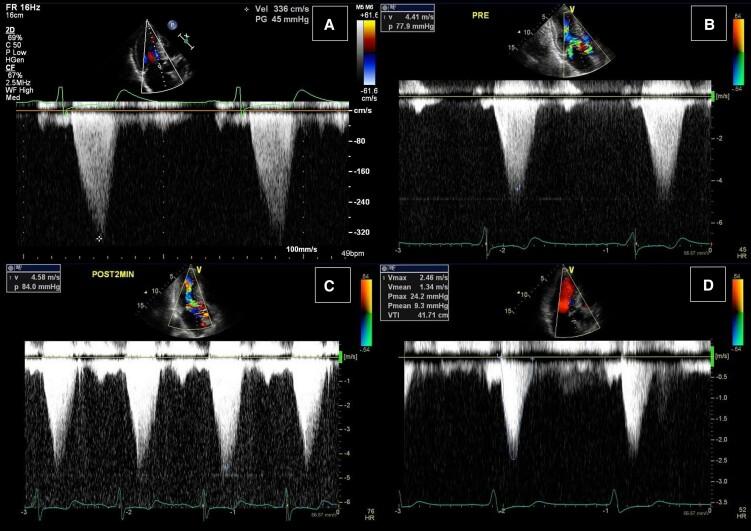

In this report, we describe the case of a patient with HOCM and anomalous papillary muscle anatomy, successfully treated by percutaneous transluminal septal myocardial ablation (PTSMA).

PTSMA effectively reduced septal myocardial thickness and LVOT gradient, with only mild residual systolic anterior motion and mitral regurgitation despite anomalous papillary muscle anatomy. Upon careful anatomical evaluation, PTSMA may be a suitable therapeutic option for patients with LVOT obstruction and mitral valve abnormalities who are poor surgical candidates.

在本报告中,我们描述了1例HOCM合并乳头肌解剖结构异常的患者,经皮腔内室间隔心肌消融术(PTSMA)治疗成功。

尽管存在乳头肌解剖结构异常,但PTSMA有效减轻了室间隔心肌厚度和LVOT梯度,仅伴有轻度残余收缩期前向运动和二尖瓣反流。经仔细的解剖学评估,PTSMA可能是LVOT梗阻和二尖瓣异常且手术风险高的患者的合适治疗选择。